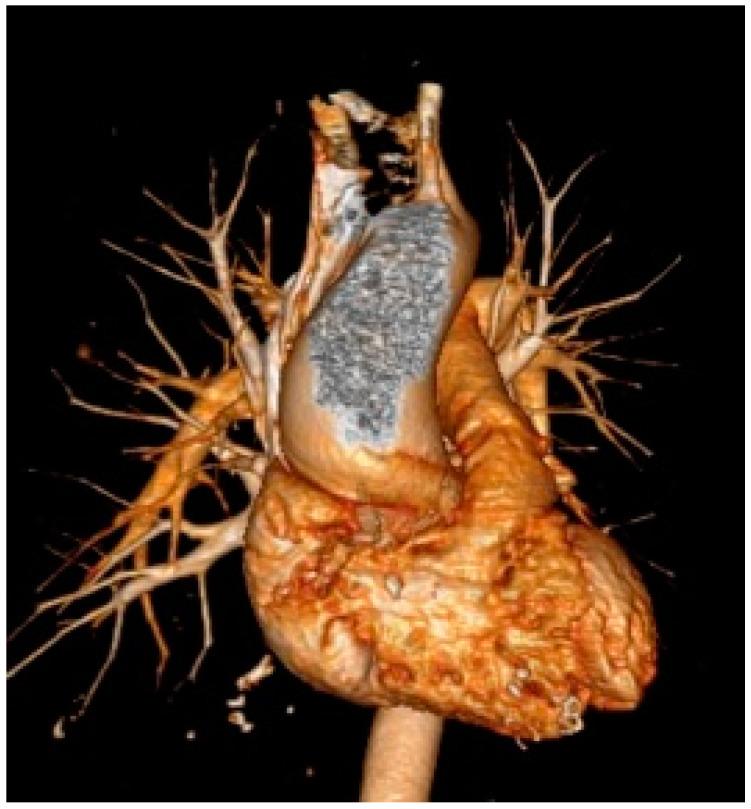

胸主动脉扩张是一种渐进性疾病,由衰老和许多病理状况(如结缔组织病、炎症性疾病、剪切应力紊乱、严重瓣膜性心脏病)引起,这些病理状况会导致弹性特性发生退行性变化,进而导致主动脉壁弹性和顺应性丧失。在运动员中也可能观察到轻度主动脉根部扩大,这被认为是对常规运动训练的正常适应。另一方面,对于具有特定遗传背景的个体,如携带与马凡综合征或其他遗传性主动脉疾病相关基因变异的个体,高强度体育活动可能会导致主动脉过度扩大并引发急性主动脉夹层。评估主动脉瓣和主动脉根部直径,以及检测遗传性主动脉疾病的致病突变后,应针对运动资格做出个性化决策。此外,遗传性主动脉疾病患者运动相关的主动脉并发症风险特征尚不明确,而且往往难以对每位运动员进行分层。本综述旨在描述规律体育活动与主动脉扩张之间的关系,重点关注二叶式主动脉瓣和遗传性主动脉疾病患者,并讨论其对主动脉疾病进展和运动参与的影响。